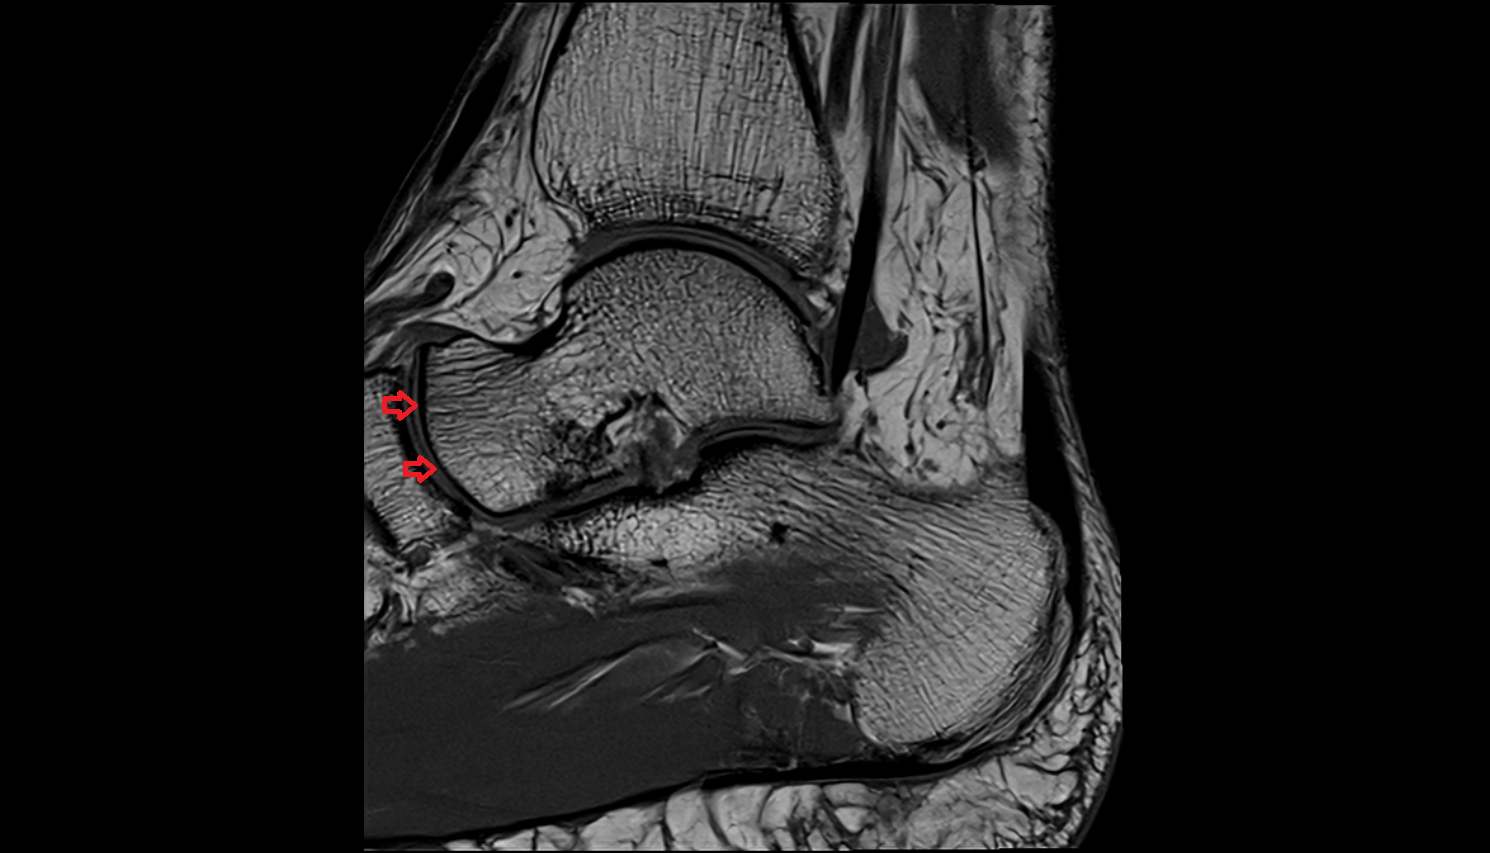

- Anterior talofibular ligament

- Posterior talofibular ligament

- Calcaneofibular ligament